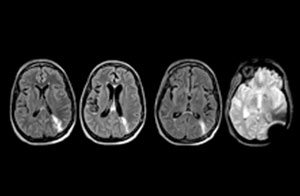

A range of protocol sheets was developed to help ensure that referring physicians order the most appropriate MRI exam. The optimized MRI protocols also include 3D contrast-enhanced imaging, allowing neurosurgeons to comfortably use the isotropic data in the operating room while performing stereotaxic surgery.

“Our results show that a dedicated MRI in the ED can be effectively implemented; patient turnaround times with MRI were on par with CT. Interestingly, even though the MRI exam protocols were shortened, this robust yet rapid scanning still yielded good quality images, further improving our workflow and almost eliminating the need for repeat scans or follow-up scans. So, we’re heading towards first time right imaging,” says Dr. Karis.